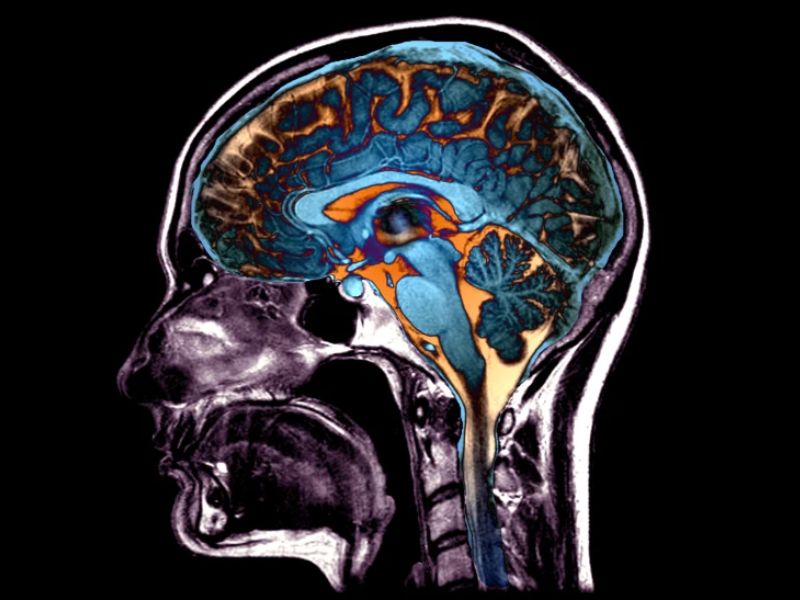

Your brain can still produce new neurons in adulthood, but how do these rare additions support cognitive function? Neurons, the cells responsible for brain function, are mostly formed before birth. While early life sees the bulk of brain development, certain regions continue generating neurons into adulthood, albeit at a slower pace. Scientists debate whether adult […]